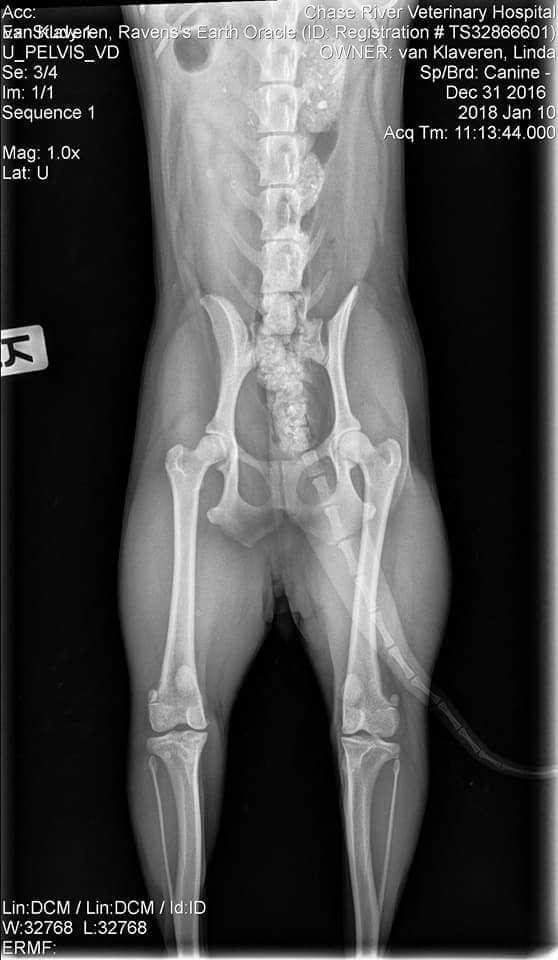

OFA Test Results:

Test Date - Jan. 10, 2018

Report Date - Jan. 15, 2018

· HIPS PRELIMINARY GOOD

· CHC-LP23/12F-VPI LEGG-CALVE-PERTHES NORMAL

· CHC-PA676/12F/P-VPI PATELLA NORMAL - PRACTITIONER